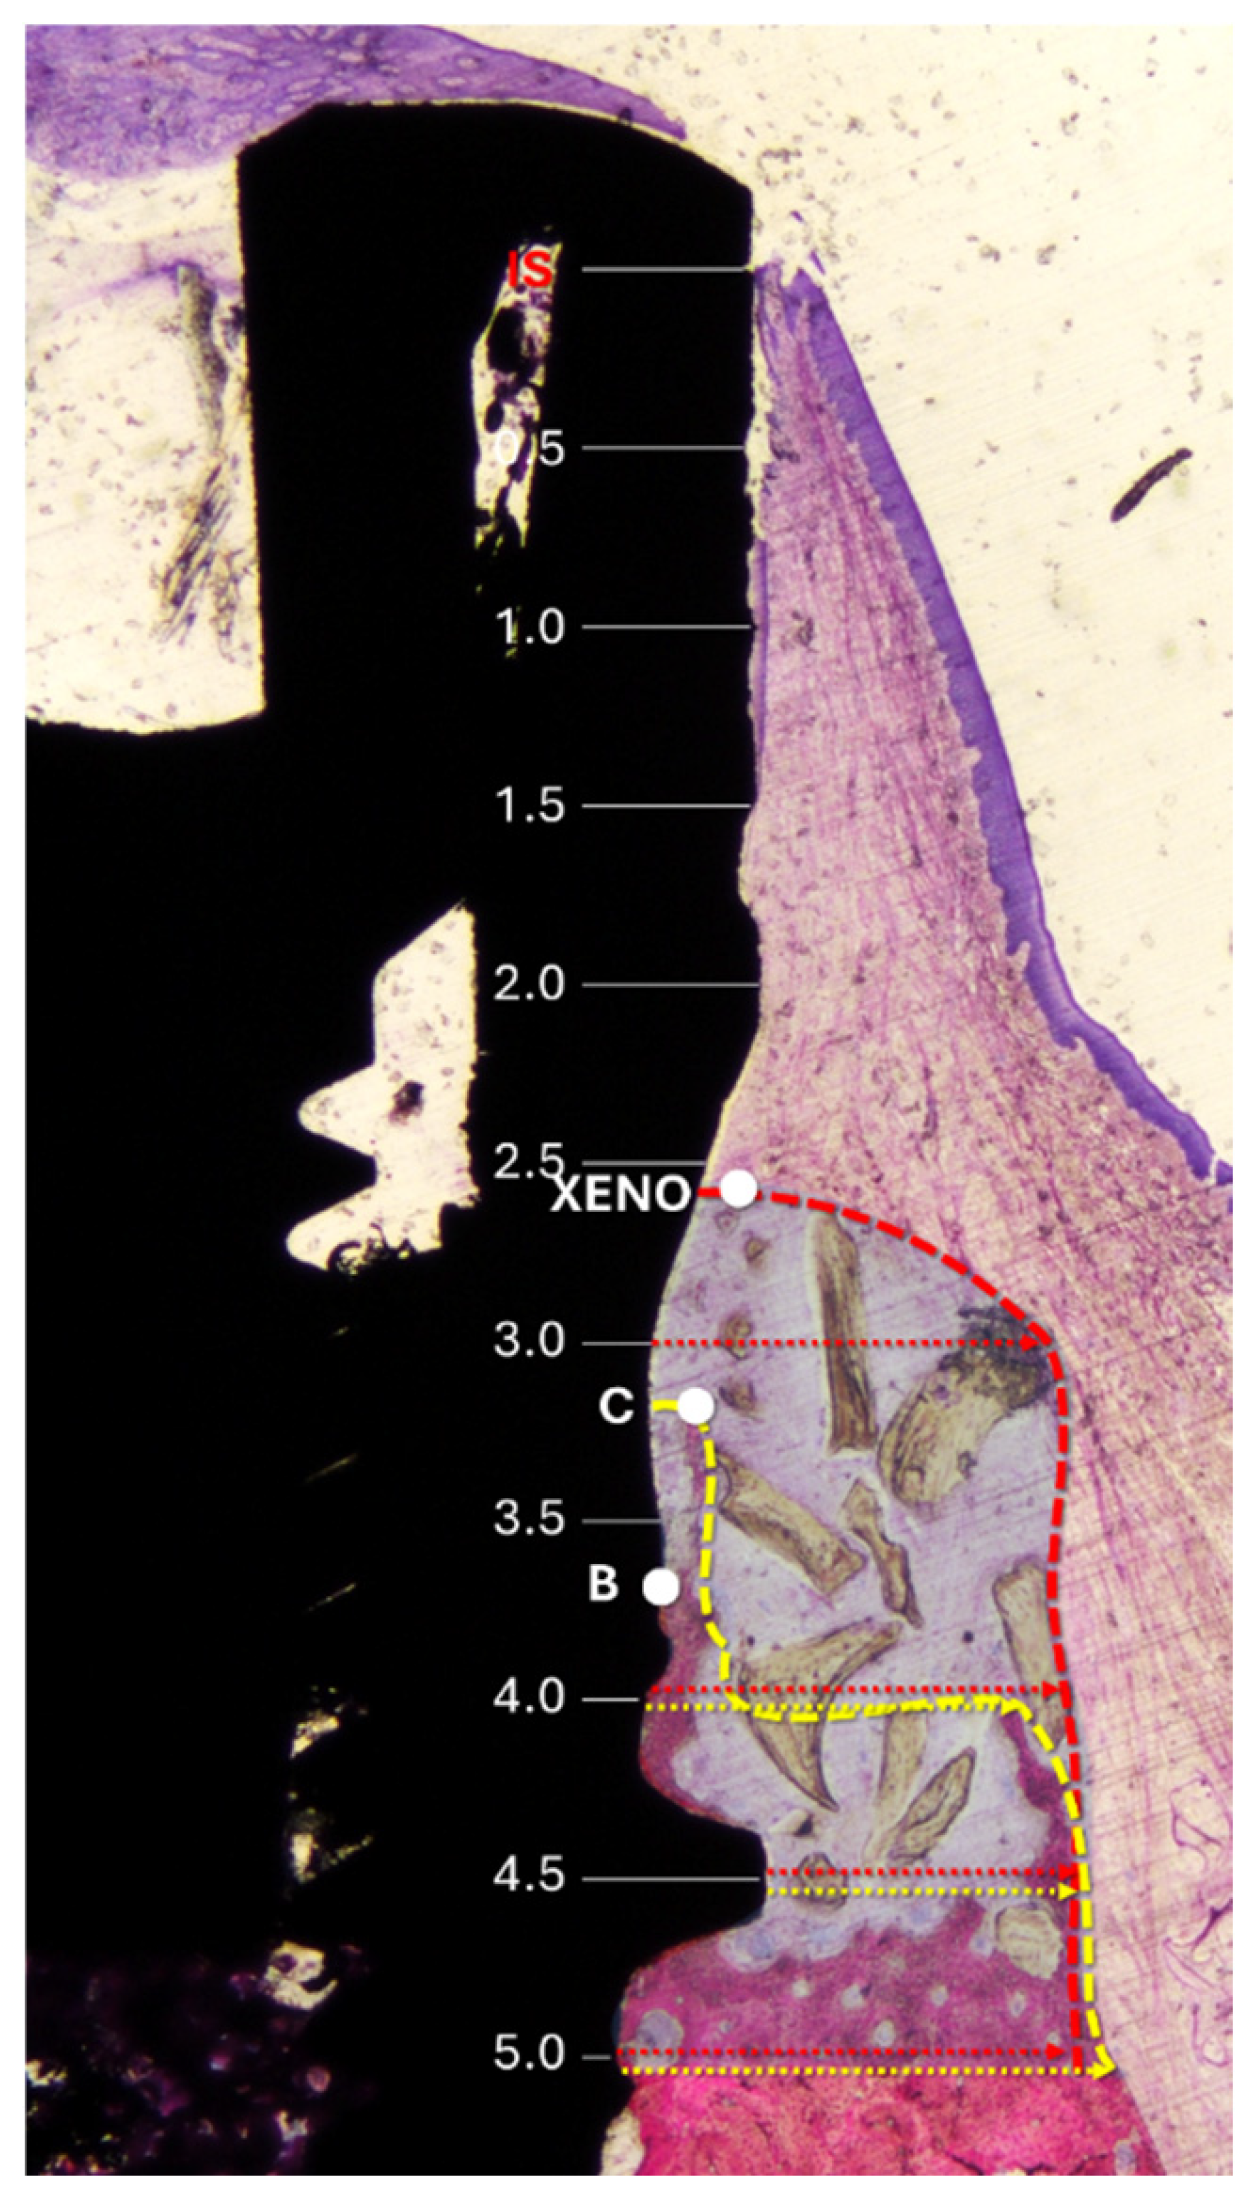

The following landmarks were used for histological measurements (Figure 2): IS (implant shoulder), C (most coronal point of newly formed bone), B (BIC; most coronal point of bone-to-implant contact), and X (most coronal level of residual xenograft granules). Vertical distances from IS to C, B, and X were assessed. The height of the regenerated bone was calculated relative to the original vertical bony defect of 5 mm.

Horizontal measurements were taken from the implant surface to the lateral margin of the new bone and the xenograft material at 0.5 mm intervals, starting from the implant shoulder and extending apically to 5 mm (Figure 3).

In addition, morphometric analysis was carried out within a region delineated by the implant surface and extending from the most coronal and lateral hard tissue to 5 mm apically to the IS (Figure 3). A point-counting method was applied by overlaying a grid on the histological sections at the microscope/computer unit. The amount of each tissue was reported as a percentage relative to the total number of evaluated points. In addition, the percentage values were converted into absolute measurements (mm2), based on the total area analyzed.

Figure 3. Histological references and measurements. IS, implant shoulder; C, top of the bone crest at the lingual aspect; B, coronal level of osseointegration. Distances from the implant surface to the most lateral extension of the bone (yellow arrows) and xenograft (red arrows) were measured at 0.5 mm intervals from IS to 5 mm apical to IS. Dashed lines delineate the periphery of the bone (yellow) and the xenograft (red). The region of interest is marked with a translucent overlay to allow for clear visualization of the underlying histological structures.